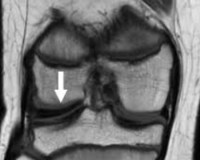

• МРТ коленного сустава. Это золотой стандарт при данной патологии. Подтверждает увеличенную толщину мениска, нарушение соотношения максимального диаметра и ширины рогов, изменение соотношения ширины мениска и большеберцового плато.